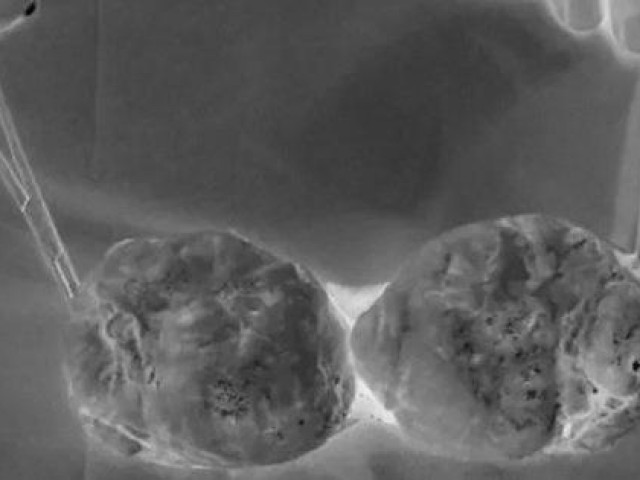

Nam người mẫu mắc ung thư tinh hoàn. Anh Vũ phát hiện mình bị ung thư tinh hoàn từ tháng 3/2019 và hiện vẫn đang tích cực chữa trị qua lại giữa Việt Nam và Trung Quốc. Từ khi dịch Covid-19, nam diễn viên điều trị tại Việt Nam.

Ung thư tinh hoàn thường dễ phát hiện đặc biệt là nam giới có thể sờ thấy u ở tinh hoàn. Đây được xem là dấu hiệu hay gặp nhất và cũng là lý do đi khám bệnh nhiều nhất.